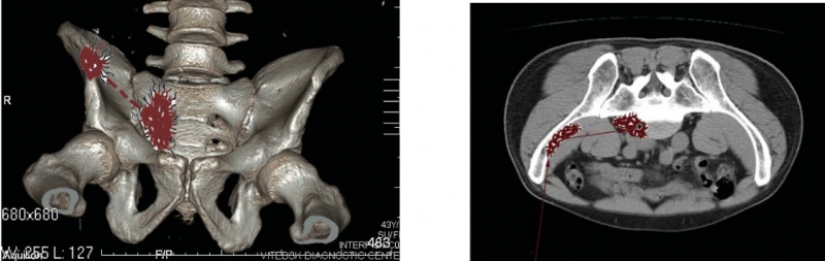

This is exactly what Pushkin's wound would look like in a picture taken with modern equipment